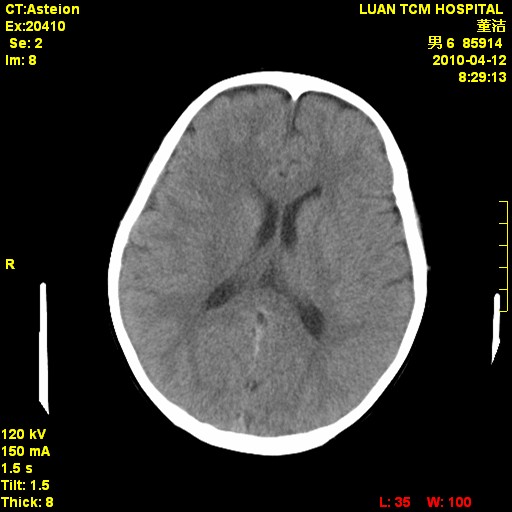

标题: PED3404:有结果,先猜猜这是啥病表现?男,12岁。 [打印本页]

标题: PED3404:有结果,先猜猜这是啥病表现?男,12岁。

考虑右侧额顶部颅内脑外血肿(edh可能)。

无病史无骨窗,无水肿无占位征象,右侧额顶部颅内血肿,或脑膜瘤。建议结合病史。

右侧额顶部自颅板向内近似半圆高密度影,周围无明显水肿,考虑:脑外血肿?脑膜瘤?淋巴瘤?